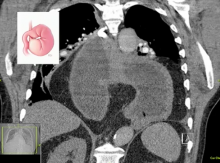

Medical treatment is often offered to most patients without chronic symptoms. In elective patients with good preoperative performance, surgical repair should be performed to resolve potential gastric or esophageal problems. In emergent cases, initial resuscitation and decompression may allow the patient to stabilize, especially when they can be endoscopically decompressed. This may allow patients additional time to recover before a surgical repair is performed prior to discharge. Surgical repair is often the best answer, but patients presenting for reoperation should only undergo reoperation if they have severe symptoms. The viability of the stomach and imaging, especially 3D imaging, can greatly influence what type of repair is needed, the repair timing, and whether or not adjunctive surgeries, such as a feeding tube placement, are required. Tenets of a good repair include: no mesh against the esophagus, crural closure, fundoplication in good candidates, gastropexy, and cruropexy. The video above reviews each step of a complex patient management algorithm (shown below) that guides the surgeon and team through the difficult decisions of managing paraesophageal hernias.